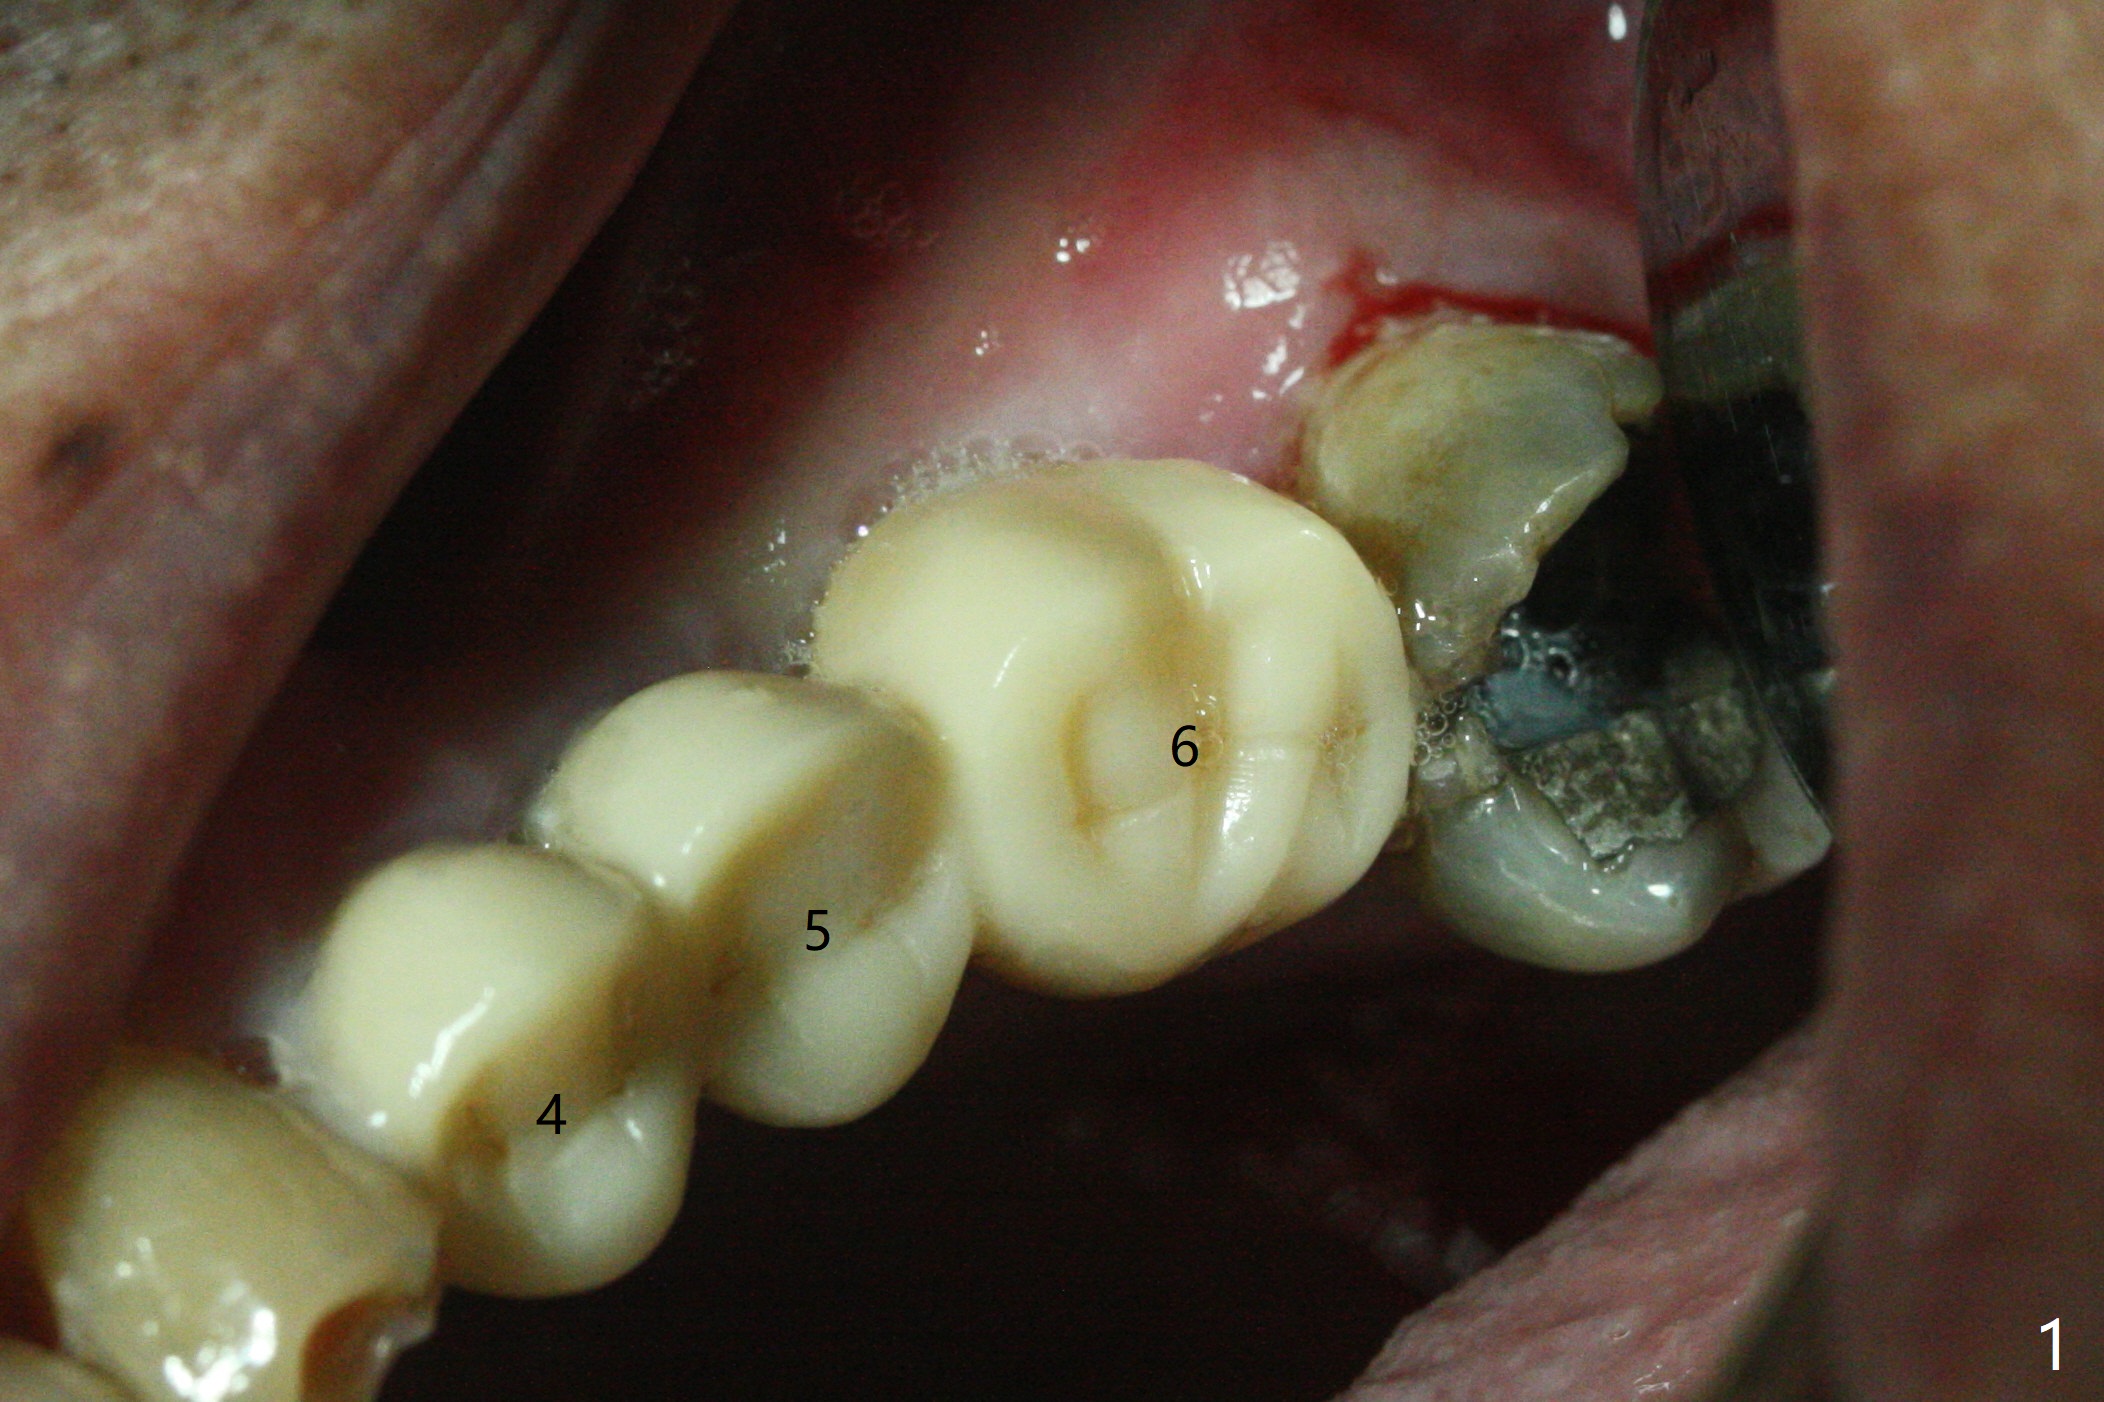

86岁男左上7折裂(图一),要求拔除,经过讨论(7拔除后,4-6悬臂桥可能断裂,对植体产生创伤,图二(左下7存在)),同意植骨。拔牙时发现中隔特别粗大(图三,五:S),三个牙槽窝根尖好像在中隔下面相互交通,擤鼻涕却没有气泡,仿佛与上颌窦没有相通。艰难清创后,放置Vanilla骨粉(图三),腭侧根特别容易填满,而颊侧根填入许多骨粉,术后CT远中颊侧骨粉尤其多(图四),上颌窦粘膜增厚(原来有季节性过敏)。术前根尖片显示远中颊侧根尖周围阴影很长(图五,六(虚线))。第二天早上鼻出血(仅有一次),今后牙槽窝明显比牙根长,清创控制深度,先放置胶原塞或PRF膜,后放骨粉。病人已经购买水牙线。术后7天树脂敷料稳定,局部卫生好(图七),骨粉好像进入上颌窦后部(图八)。术后1.5个月树脂敷料仍在原位,很容易撤除,牙槽窝愈合(图九),骨粉好像没有丢失(图十)。